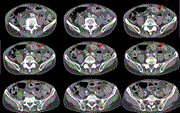

Prophylaxis and treatment of acute and chronic postoperative inguinal pain (CPIP)—association of pain with compression neuropathy

René Gordon Holzheimer and Nikolai Gaschütz

Journal of Surgical Case Reports, Volume 2020, Issue 7, July 2020, rjaa143, https://doi.org/10.1093/jscr/rjaa143